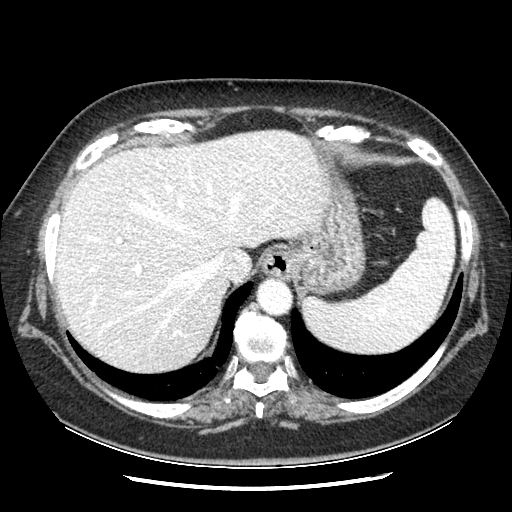

Original VENOUS CT scan

Full window (WL 1023.5, WW 4095 β†’ Low βˆ’1024, High +3071)

Mediastinum window (WL 40, WW 400 β†’ Low βˆ’160, High +240)